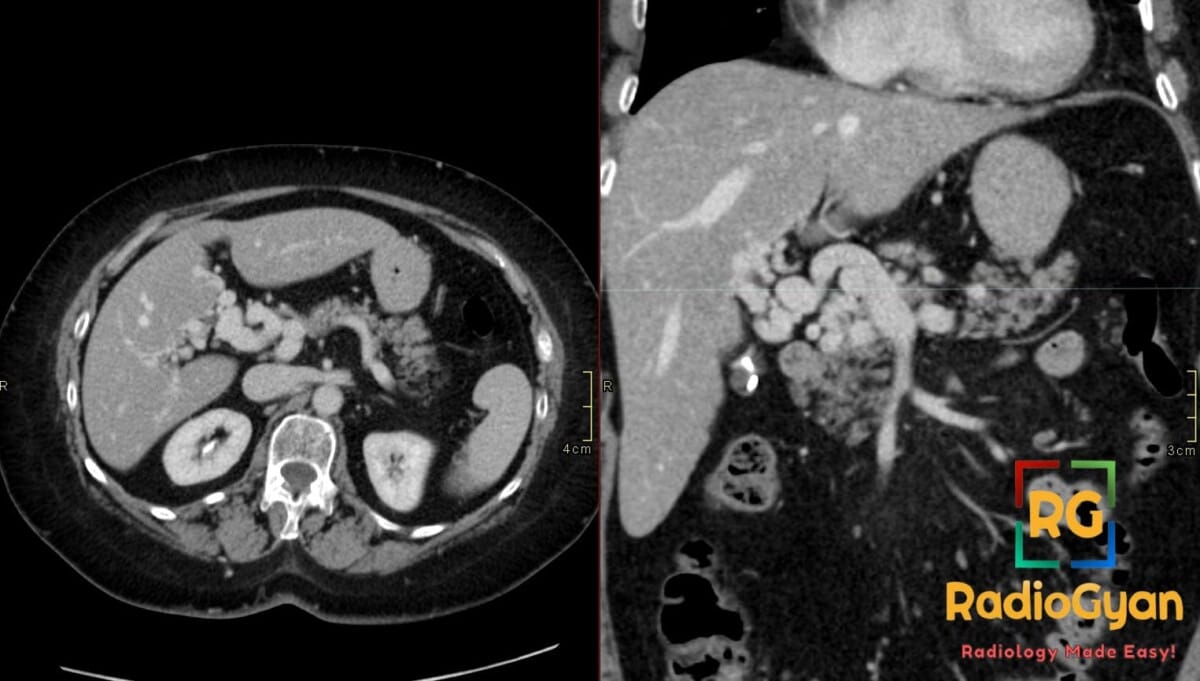

42 yr male with a history of neonatal umbilical vein catheterization presenting with hematemesis and splenomegaly.

Diagnosis: Cavernous transformation of the portal vein

- CT: Nonvisualization of the main portal vein trunk replaced by numerous tortuous periportal collaterals (cavernoma); may appear as a solid tumor-like enhancing hilar mass; associated signs include splenomegaly and gallbladder varices.

- Signs: Portal cavernoma: A sponge-like mass or tangle of enhancing vessels in the porta hepatis representing dilated periportal collaterals.